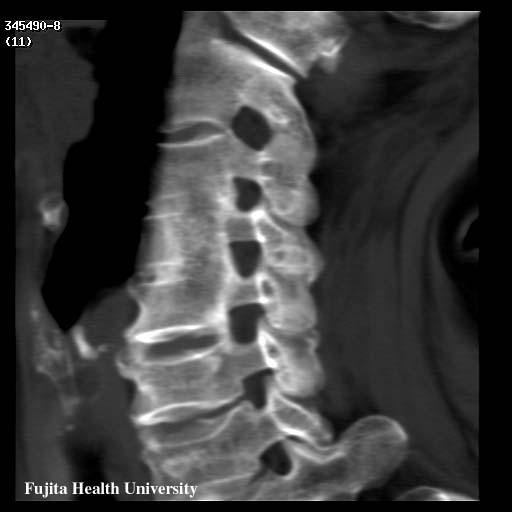

Cervical OPLL: Post surgical follow-up

0.5mmx4, Pitch 3, 60-seconds, 135kV, 130-mAs:

Re-projection image